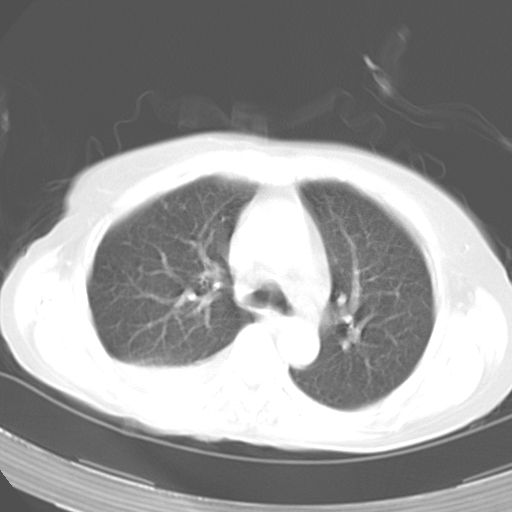

以下是引用dyqct在2006-12-7 21:08:00的发言:[br]考虑:1、肝内外胆管多发性结石伴肝左叶外侧段肝萎缩;[br] 2、右膈下多发脓肿;[br] 3、右侧少量胸腔积液、斜裂积液;[br] 4、左肾囊肿。

以下是引用jiazh在2006-12-7 20:37:00的发言:[br]肝脏周围半狐形低密度影,肝脏表面受压推移,考虑膈下脓肿可能性大;2、右侧胸腔积液

以下是引用拾荒者在2006-12-7 21:44:00的发言:[br]肝内外胆管多发结石,右膈下多发脓肿,右胸膜腔及叶间裂积液,左肾囊肿。[br] [br]